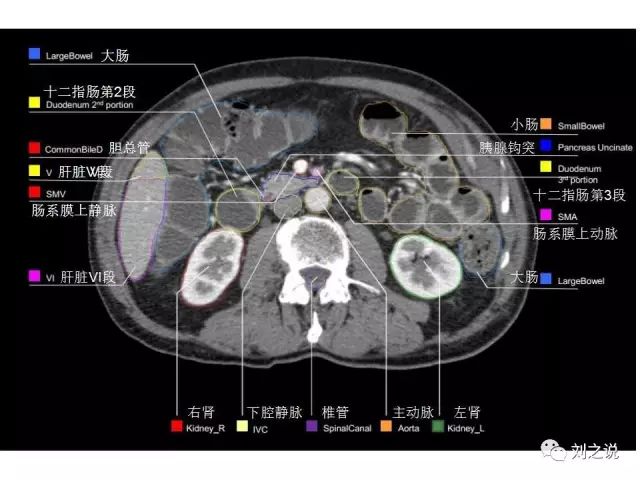

【解剖】高清实用 腹部CT断层

参考RTOG共识和3D-body解剖。